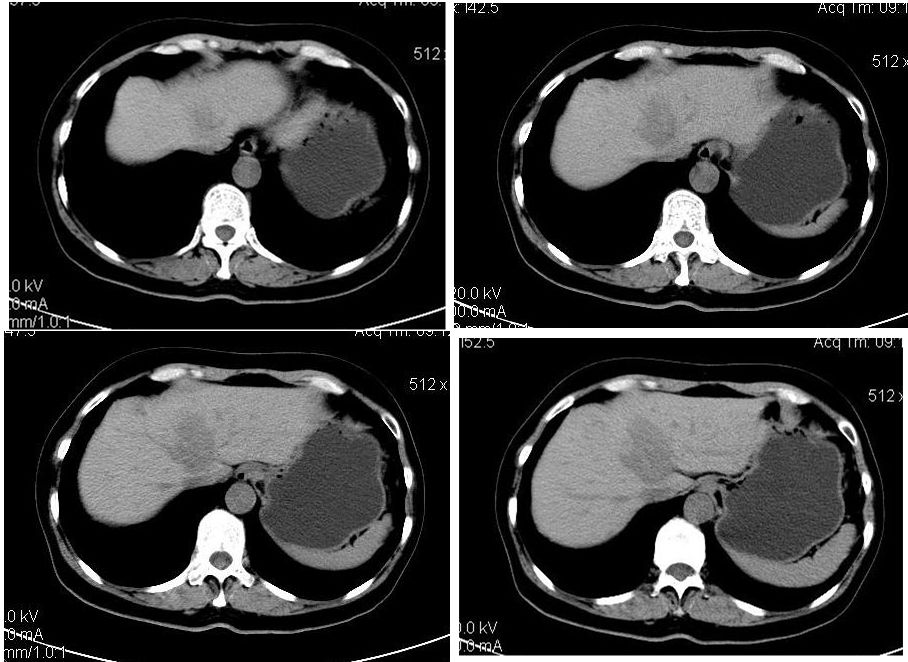

患者,女,65岁,住院准备甲状腺腺瘤用术,术前常规发现肝脏占位,ct增强扫描。

平扫

动脉期

门脉期

延迟扫描

肝左叶内侧段低密度灶,增强明显快进快出表现,考虑:肝癌。

学习了,这可能是脂肪含量少的血管平滑肌脂肪瘤,因血管丰富所以动脉期密度升高明显,但该患无肝硬化表现,所以,诊断肝癌,依据不足.谢谢上传.对今后工作是一个提醒.